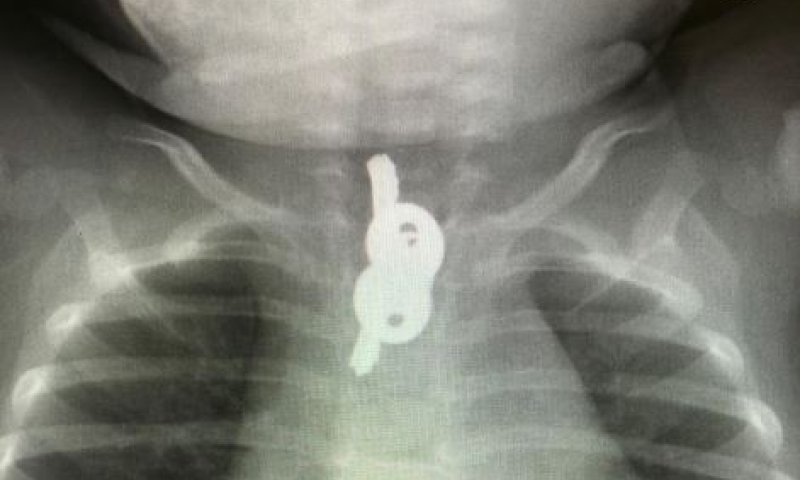

במהלך ראש השנה הובא למיון ילדים בשערי צדק תינוק כבן 10 חודשים, לאחר שבצילום רנטגן שבוצע במרפאת טרם התברר שבלע זוג מפתחות.

ההפתעה שציפתה להורים הייתה גדולה מאוד. בצילום נראו זוג מפתחות בוושט בגובה החזה. התינוק הובהל מידית למרכז הרפואי שערי צדק ושם כאמור הוצאו המפתחות ללא נזק.

ד"ר אוהד כהן, רופא אף אוזן גרון מהצוות שטיפל בילד סיפר: "מיד שהתקבל התינוק ולאחר שאבחנו כי המפתחות תקועים בוושט במשך למעלה משבוע הוא הובהל מיד לחדר ניתוח על מנת להוציאם לפני שייגרם נזק נוסף. אני שמח שהצלחנו להוציא את המפתחות ללא סיבוכים".